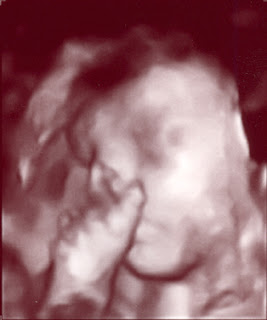

3D Bryan at 25 weeks